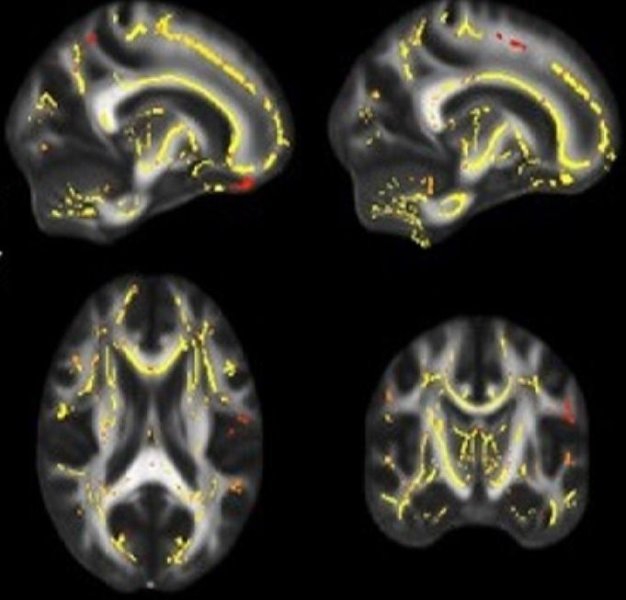

El método del estudio fue el siguiente: Se analizaron la integridad de la materia blanca, el funcionamiento cognitivo (memoria y funciones ejecutivas) y la capacidad aeróbica (VO2 máx) de 81 personas de 60 a 70 años con deterioro cognitivo ligero y 26 personas, en el mismo rango de edad, cognitivamente normales. Las asociaciones resultantes determinaron que niveles de baja aptitud física están vinculados con materia blanca debilitada, lo que a su vez está relacionado con un deterioro en el desempeño del sistema nervioso central. Por otro lado, niveles elevados de aptitud cardiorespiratoria se asociaron a una integridad más fuerte de la materia blanca y, por tanto, a un mejor desempeño cognitivo. A diferencia de estudios previos, donde no se realizaban pruebas de aptitud física de manera directa, sino que se dependía de cuestionarios personales, la medición precisa del consumo máximo de oxígeno de cada uno le da a los resultados un mayor margen de confiabilidad.

Baja aptitud física vinculada con debilidad en las fibras del cerebro y un mayor riesgo de demencia